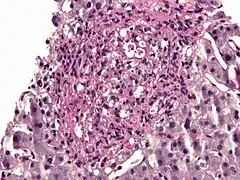

| Histopathology of Histoplasma capsulatum, H&E stain, showing organisms surrounded by halos, in a granuloma of epithelioid histiocytes. | |

The budding yeast cells formed in infected tissues are small (about 2–4 µm) and are characteristically seen forming in clusters within phagocytic cells, including histiocytes and other macrophages, as well as monocytes. An African phylogenetic species, H. duboisii, often forms larger yeast cells to 15 µm.